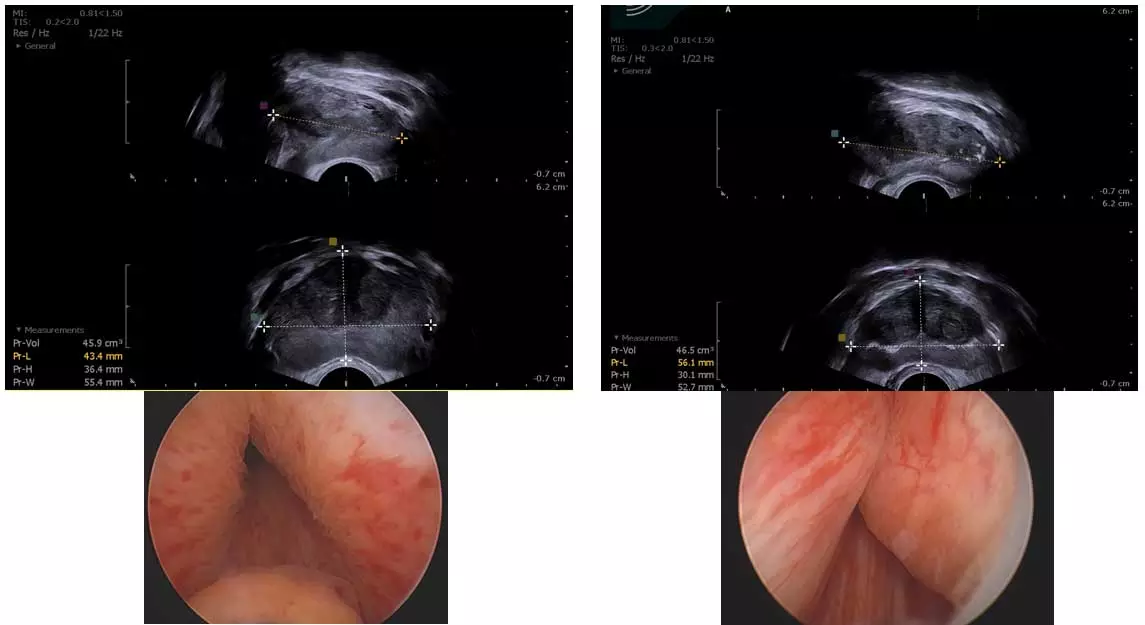

진료실에서 실제로 초음파 영상을 제시하면 환자들도 “가운데 막힌 게 보인다”라며 바로 이해한다. 특히 가운데에 잠자리 눈처럼 동그랗게 알맹이가 보이고 이행대가 바깥과 확연히 구분돼 보이면, 소변 길이 막혀 있을 가능성이 높다. 그래서 크기가 작아도 소변을 약하게 보는 환자가 있고, 반대로 크기가 크더라도 의외로 소변을 잘 보는 차이가 생긴다.

또 하나 중요한 것은 ‘방광출구 폐색’이다. 전립선이 단순히 옆으로 커지는 것이 아니라 방광 쪽으로 자라며 들어가는 경우가 있다. 이를 ‘방광 내 돌출’이라고 하는데, 이런 형태에서는 전립선 크기가 크지 않아도 약물 치료 효과가 떨어지는 경우가 많다. 이때는 막힌 부위를 제거하는 치료가 더 도움이 될 수 있다.